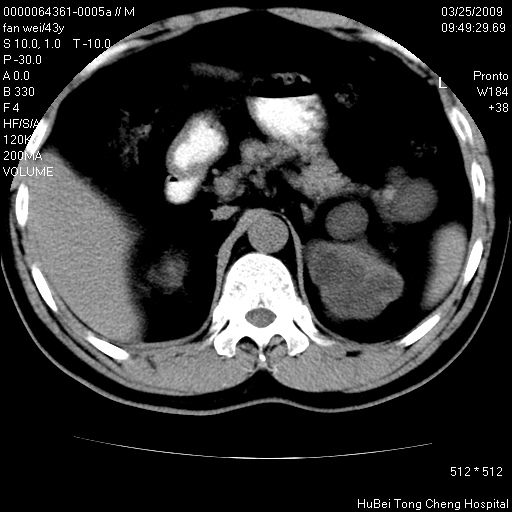

患者 男,43岁。左侧腰部不适两天。平素健康。无家族遗传病史。

腹部彩超提示:1)轻度脂肪肝。2)左肾多发囊性占位性病变;建议行进一步检查。

临床诊断:左肾多发囊性占位性病变,性质待定(多发肾囊肿?)。

双肾ct轴位平扫+增强扫描(层厚10mm,螺距1.0,重建间隔10mm),图像如下: